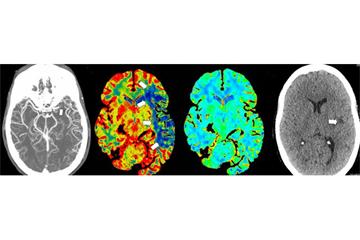

Identifying patients eligible for MT - removing a blockage in a large blood vessel in the brain - relies on specialist radiological image interpretation. The OUH is one of 24 stroke centres across England taking part in an evaluation led by the Oxford AHSN of e-Stroke, created by Brainomix, which uses artificial intelligence (AI) technology to share high quality brain scans quickly and securely, generating unique outputs that help stroke clinicians make swift decisions relating to treatment and transfer.

Previously, CT brain scans had to be reviewed by a specialist at a computer in a stroke unit. Now they can be seen within a few minutes of being processed via web interface or mobile phone app and advice given immediately. Earlier identification and speedier decision times increase the window of opportunity for MT. Reducing the time between the patient arriving in hospital and being referred for treatment is crucial in securing full recovery after a stroke.